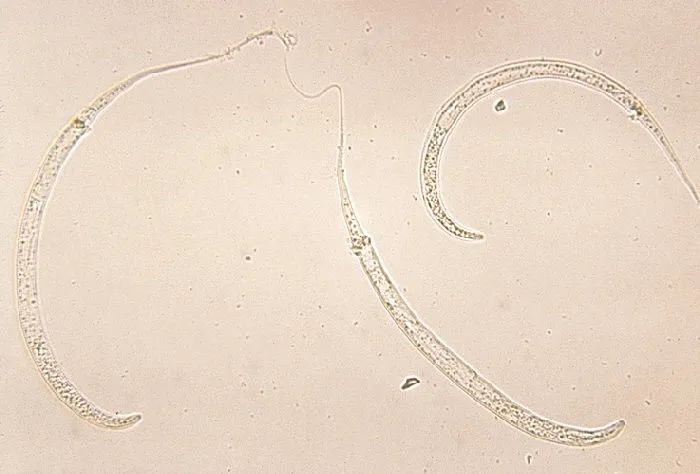

麦地那龙线虫 | CDC / Wikimedia Commons

这种生物就犹如它的名字一样让我们一头雾水,它到底是什么生物?是龙还是虫?而它的名字也困惑了我好久,到底是麦地那·龙线虫还是麦地那龙·线虫?拉丁文学名Dracunculus medinensis揭示了答案:麦地那·龙线虫才是正确的读法。

龙的体型非常巨大,而继承龙之名的麦地那龙线虫,同样也是已知最大的线虫之一,体长可以超过一米。我们的祖先有一句至理名言:“不怕贼偷就怕贼惦记。”试想在不知不觉当中,你体内潜伏着一条“恶龙”,它不仅无情的吞噬着你的血肉,还会在未来的某一天释放强烈的“暗黑魔法”让你痛不欲生,想想就会让我不寒而栗......

麦地那龙线虫的幼虫生活在水中,它们会寄生在一些微小的桡足类动物(通常俗称为剑水蚤,大型种类也被作为观赏鱼的活饲料也将其称为青蹦)体内,当人喝了含有剑水蚤的水,就会被感染。剑水蚤被胃液消化掉后,龙线虫的幼虫会钻入消化道的表皮,通过循环系统进入你的体内,吸收人体组织生长发育。当然“恶龙”会分泌一些物质混过免疫系统,同时也抵消疼痛感,这样即使恶龙的体长达到1米,我们也不会察觉到它的存在......